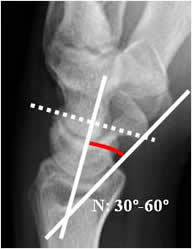

Angulo escafolunado:

Tiene una amplitud normal entre 30º y 60º. El eje del escafoides se traza uniendo los bordes anteriores superior e inferior y el del lunado, por una línea perpendicular a la unión de sus polos distales.

En la inestabilidad tipo VISI (volar inestabilidad del segmento intercalado), hay desplazamiento anterior de los huesos escafoides y el lunado, que produce disminución del ángulo escafolunado. (27, 28). (Fig 51 y 52).

Fig 51. Angulo escafolunado.

A: Rx lateral de muñeca. Intersección entre los ejes de los huesos escafoides y lunado.

Fig 52. Inestabilidad tipo VISI.

A: Rx lateral de muñeca. Disminución del ángulo escafolunado, por inestabilidad tipo VISI.